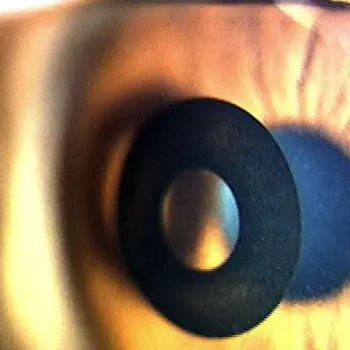

사람은 누가나 나이가 들면 눈에 노화가 오게 되는데, 노안의 원인은 노화에 의한 원인이 대부분입니다. 노화가 진행됨에 따라 눈의 수정체도 탄력성이 떨어지게 되어 수정체의 초점 조절 능력이 떨어지게 되는데, 이로 인해 가까이에 있는 글씨나 사물이 보기 어려워지게 되는 현상이 바로 노안입니다.

눈은 수정체의 굴절로 먼 곳과 가까운 곳을 볼 수 있습니다. 수정체가 두껍게 되면 빛의 굴절각이 높아져서 가까운 것을 볼 수 있게 되고, 수정체가 얇아지면 빛의 굴절각이 완만하게 되어 멀리 이는 것이 잘 보이게 되는 원리인데, 노화로 인해 수정체의 초점 조절이 잘 되지 않게 되는 것이 노안의 원인입니다.